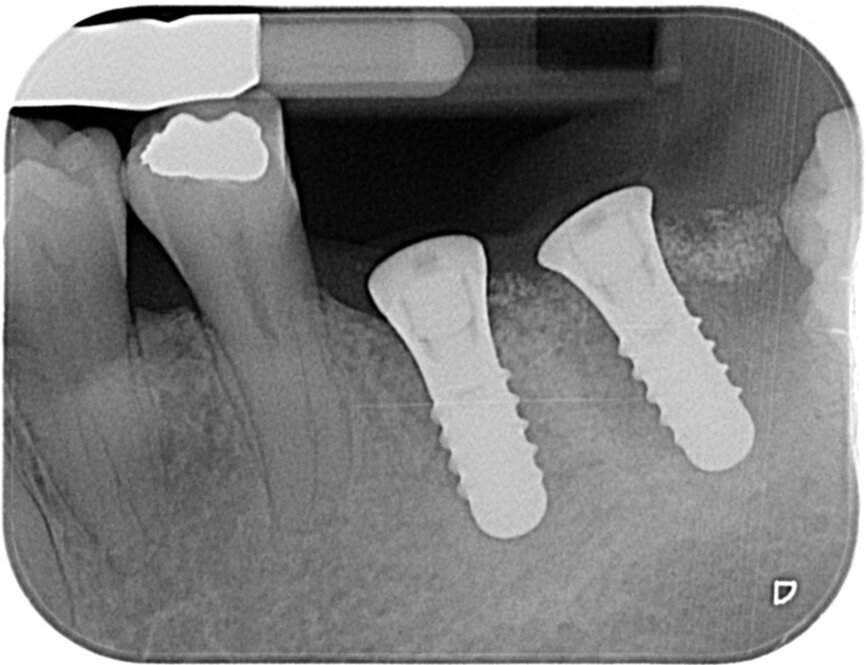

Fig. 8: Postoperative radiograph of implant placement.

We are routinely used to 2-D radiographic imaging techniques in dentistry, but with the availability and access to CBCT scanning devices now, we are able to assess bone quantity and quality of proposed implant surgical sites. With ever-reducing doses of 3-D imaging and improving accuracy, we are able to use CBCT scans, combined with clever software packages such as coDiagnostiX (Dental Wings), to plan safe and accurate implant placement and restoration. We are able to preoperatively plan precise implant placement with safe surgical margins away from important anatomical structures, such as the inferior alveolar nerve or maxillary sinus. From this, we are then able to design and either mill or print a surgical guide to use for precise implant placement.

Even with assisted surgery or guided surgery, there are sometimes certain restrictions that prevent us from achieving the most ideal implant placement, such as this case shown where posterior access in the second molar region was reduced, so achieving the perfect parallel was extremely difficult.